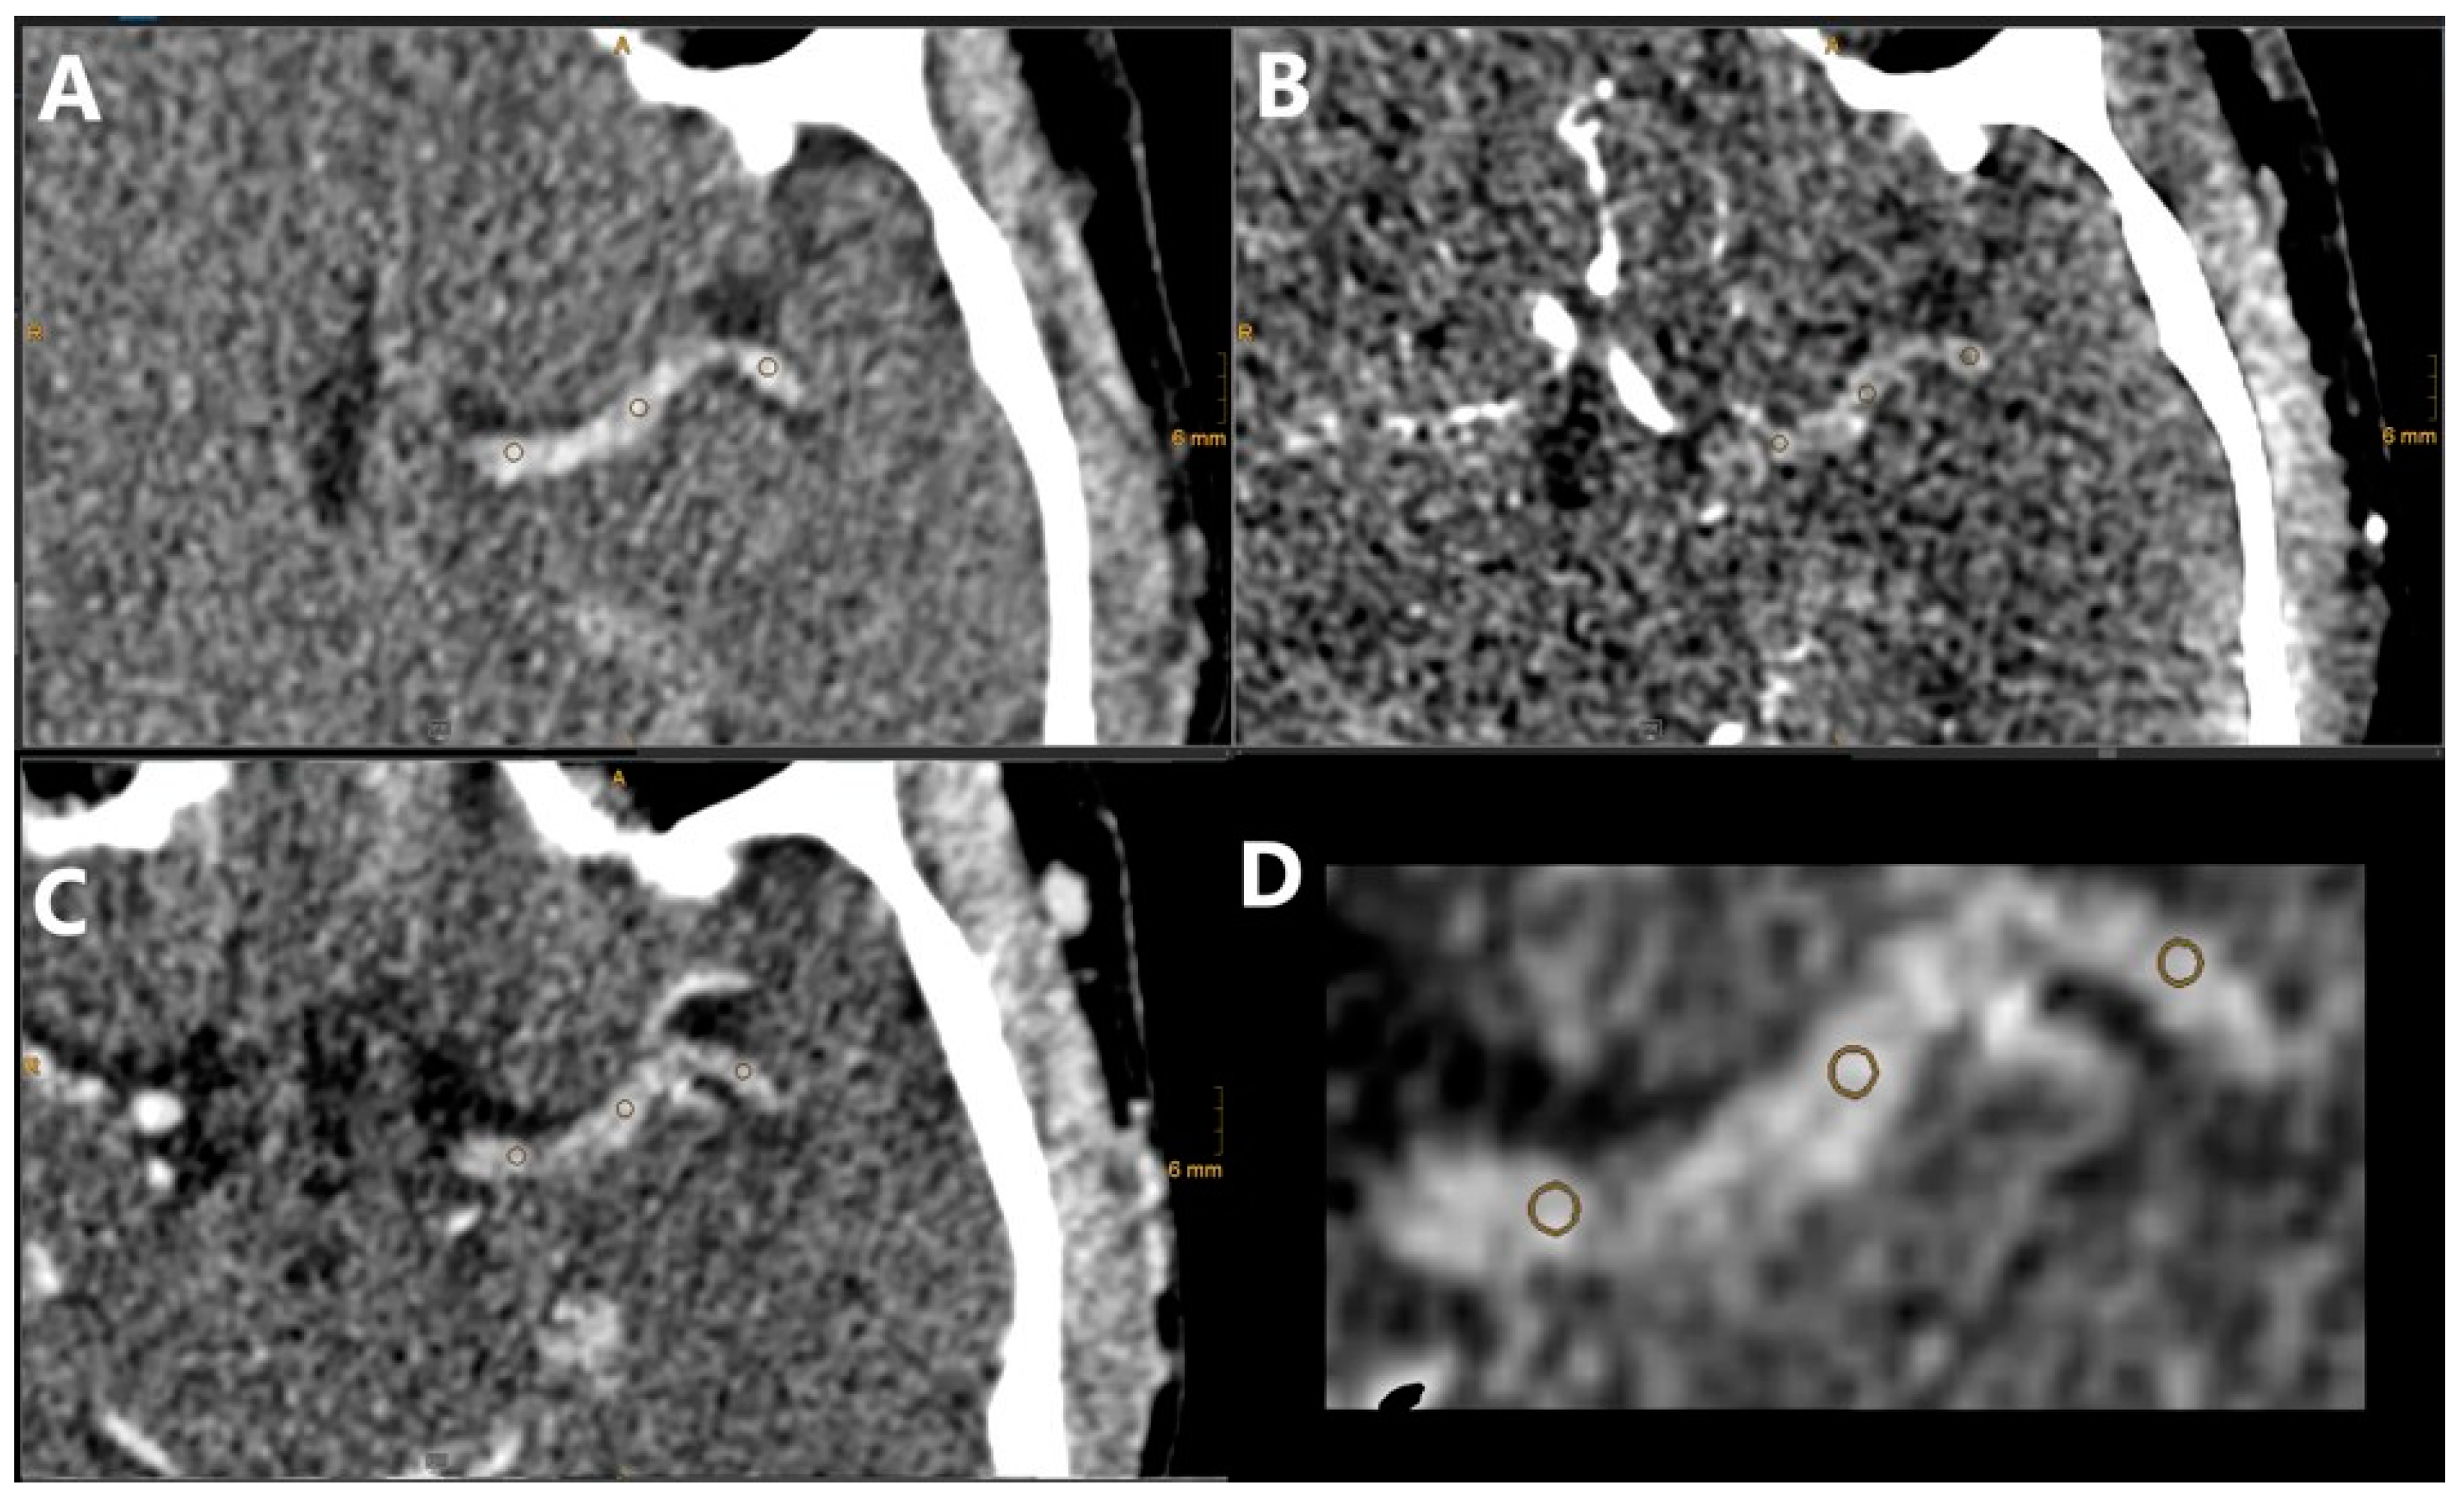

The analysis of the CT images was performed on our clinical PACS system (DeepUnity R20, Dedalus, Florence, Italy). The built-in 3D co-registration tool (3D Fit) was used to align the NCCT, CTA, and CTV series with manual corrections if necessary. A multiplanar reformat tool was used, where needed, for full visualization of the clot. The location of the clot was noted and the length was measured using a combination of hyperdensity for the NCCT and distal flow for the CTV. The TAI was measured similarly as by Santos et al. [4]. Three regions of interest (ROI) were placed over the length of the clot with a size of 1 mm each, and the density value in Hounsfield units (HU) was noted in the three imaging series simultaneously (Figure 2). This assessment was performed by an interventional radiologist with 10 years of experience (DT).

Figure 2. NCCT (A), CTA (B), and CTV (C) images of our clinical protocol for a patient with distal ICA and proximal M1 occlusions on the left side. The TAI was calculated between the NCCT and CTA, NCCT and CTV, and CTA and CTV results using spherically defined ROIs as illustrated in (D), overlaid on the NCCT image. The ROIs were defined manually by considering the clot area based on the NCCT and CTV results.